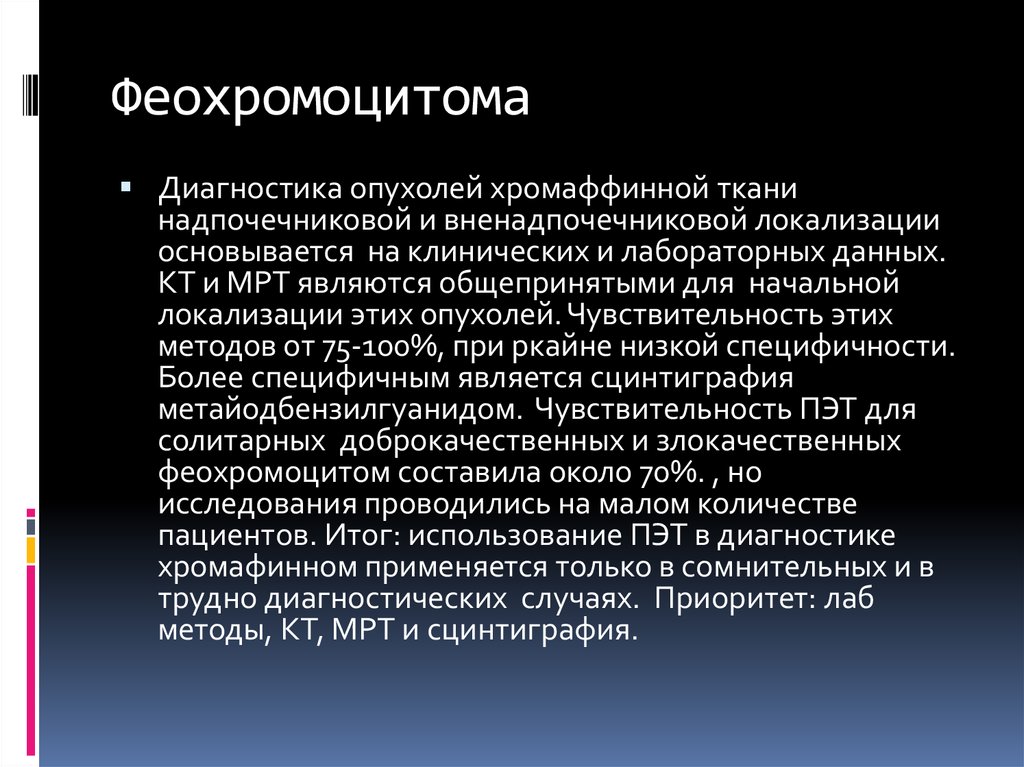

Кт энтерография тонкого кишечника. Образование брыжейки тонкого кишечника кт. Опухоль Толстого кишечника на мрт. Феохромоцитома диагно. Феохромоцитома методы диагностики. Феохромоцитома локализация. Исследования при феохромоцитоме.

Феохромоцитома диагно. Феохромоцитома методы диагностики. Феохромоцитома локализация. Исследования при феохромоцитоме. Опухоль шишковидного тела. Опухоль шишковидного тела в головном мозге. Пинеалома опухоль шишковидной. Опухоль шишковидной железы симптомы.